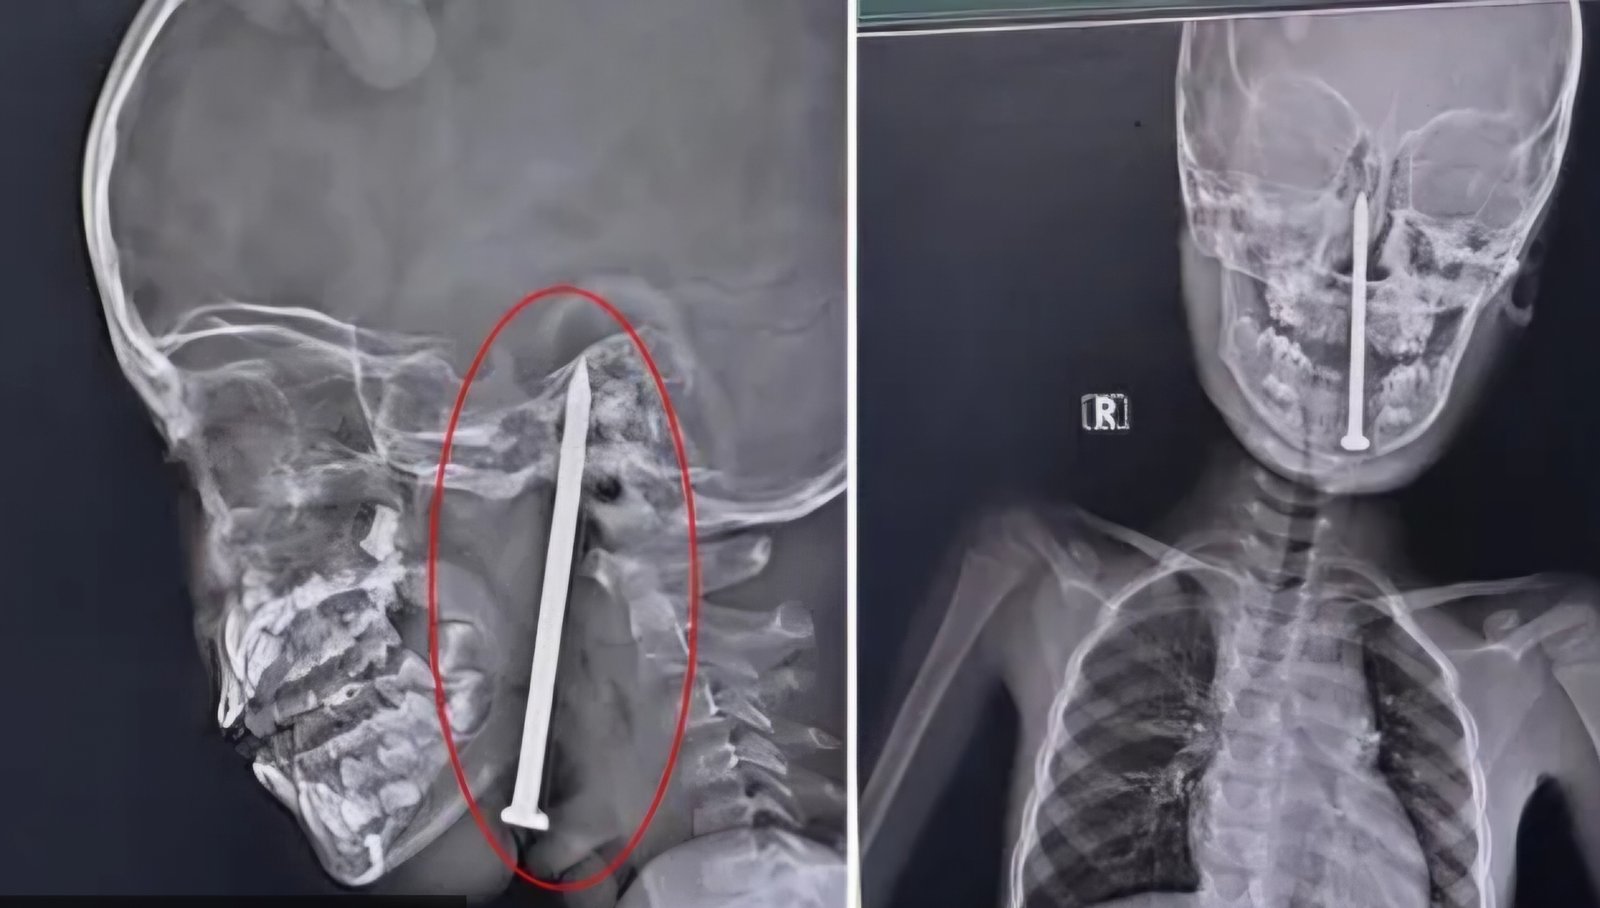

Liječnici su napravili detaljne pretrage, uključujući MR i CT snimke, koje su pokazale da je čavao, dugačak osam centimetara, prošao vrlo blizu vitalnih krvnih žila u dječakovom mozgu. Tim neurokirurga odlučio je poduzeti gotovo nemoguću misiju: izvedbu složene operacije s ciljem spašavanja dječakovog života.

Operacija je trajala deset sati i uključivala je uporabu naprednih mikrokirurških tehnika i neuronavigacije, kako bi se pažljivo izvukao čavao bez nanošenja štete osjetljivim dijelovima mozga. Nakon napornog i zahtjevnog zahvata, dječak je stabilan i trenutno nije u životnoj opasnosti, piše net.hr, a njegovo stanje se uspješno oporavlja.